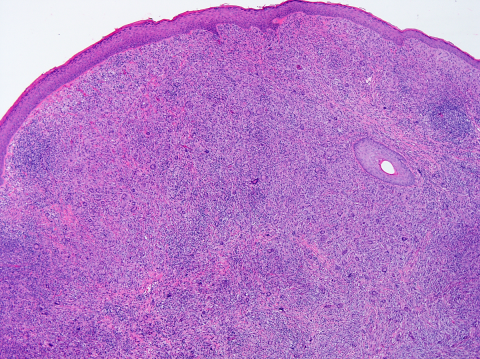

The pathogenesis of JXG is thought to be of reactive origin, namely local tissue injury that evoked a histioxanthomatous reaction.[13] Histologically, the cutaneous infiltrate includes a mixture of foamy histiocytes, lymphocytes, fibroblasts and multinucleated giant cells, including Touton-type giant cells, with a moderate amount of collagen deposition (Figures 4-5). A Touton giant cell is a multinucleated cell that contains a wreath of nuclei surrounding homogeneous cytoplasm, with a rim of foamy cytoplasm peripheral to the nuclei. Other inflammatory cells may be present to varying degrees.[16] JXG cells stain positive for CD68, have variable reactivity for factor XIIIa and stain negative for CD1a, S100, CD20716. JXG does not carry BRAF V600E mutation, except in patients with both Langerhans’ cells histiocytosis (LCH) and JXG (non-Langerhans' cells histiocytosis) diseases and in the aggressive forms of JXG.[8] Development of JXG after chemotherapy for LCH has been reported in 11 patients.[16] One theory proposed the coexistence of LCH and JXG could be the result of chemotherapy-induced maturation of Langerhans’ cells into macrophages, in particular foamy cells.[17] Another theory hypothesized that JXG may be triggered by LCH lesions through the production of a cytokine storm.[9][16]

The classic histopathologic findings include multinucleated Touton giant cells in addition to epitheloid histiocytes, lymphocytes and eosinophils (Figures 4-5). However, Touton giant cells are not mandatory for the diagnosis of JXG. In early JXG, small- to intermediate-sized mononuclear histiocytes display a compact sheet-like infiltrate; the lipidization of histiocytes is not detectable and Touton giant cells are rarely found. The pale eosinophilic cytoplasm is sparse to moderate and does often not contain any lipid vacuoles or only fine vacuoles.[24]